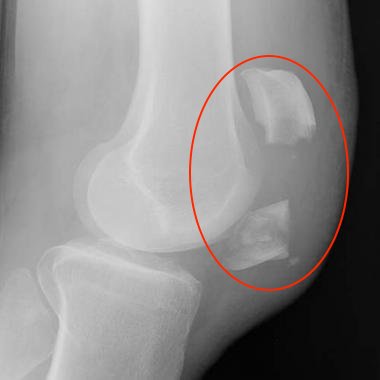

Como é feito o diagnóstico? Além da história clínica e do exame físico, a utilização de alguns exames de imagens auxilia no diagnóstico e planejamento da conduta terapêutica. A radiografia (RX) é o exame mais acessível e o mais utilizado para essa finalidade. A tomografia é muito útil para uma melhor avaliação do padrão de fratura.

Como o padrão da fratura é classificado? Apesar de cada fratura ser diferente de uma pessoa para a outra, muitas apresentam padrões semelhantes. Tais padrões permitem criarmos uma classificação que orienta os médicos na condução do tratamento. Os principais aspectos observados são o Desvio dos Fragmentos (“quanto mais afastados os pedaços da fratura, mais difícil o tratamento”, por exemplo) e o Traço da Fratura (fratura em formato de “estrela”, fratura “transversa”, “multifragmentada” etc).